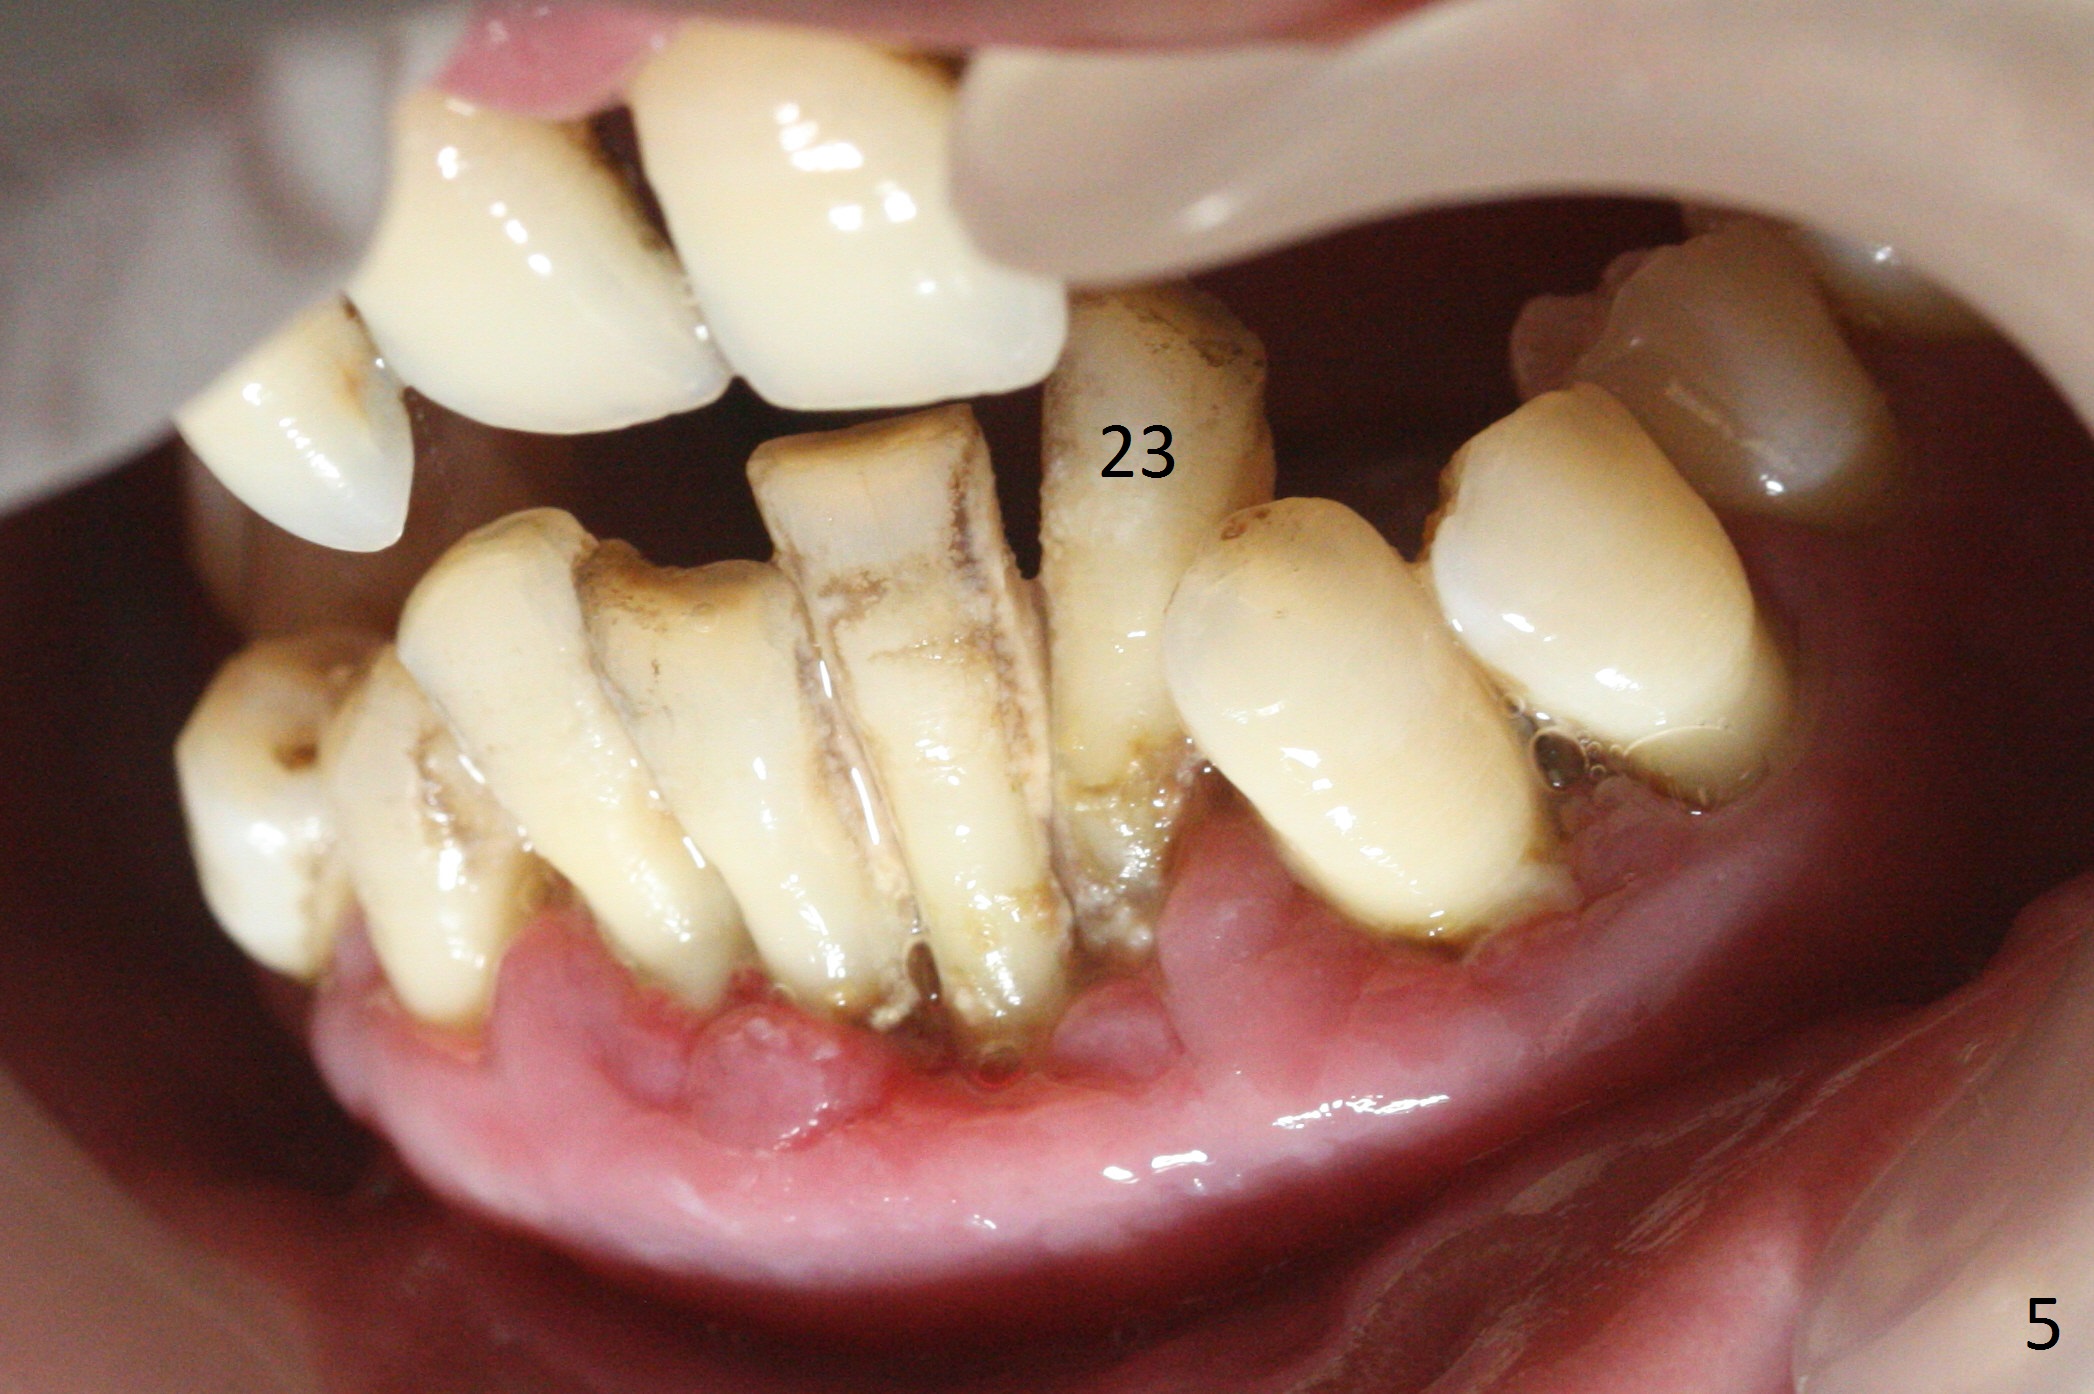

A 36-year-old man (ex-smoker) has advanced chronic periodontitis (Fig.1-5). His chief complaint is "I cannot chew on the right side now because of pain (Fig.1: #3 abscess <) and the bottom front teeth are loose (Fig.2,5: #23-26)". He has not masticated on the left side because of the mobile teeth. Due to finance, implants will be placed at #3,4 (Fig.12), 23 and 26 at the appointments of scaling & root planing.

Class II Division II malocclusion (Fig.2,6) will make it difficult to restore #23-26 implant-supported FPD. Although the teeth #7-10 may need to be replaced later (Fig.7,8), enameloplasty will be conducted for #7-10 (Fig.9 white area; Fig.12 black circles (gross reduction)) prior to #23-26 extraction and implant placement (Fig.10). To be flexible in restoration (angulation) and possible future hybrid denture, 2-piece narrow implants will be placed (3.0 or 3.3 mm) instead of 1-piece ones. In fact CBCT shows that the narrowest regular implant (3.8 mm) can be placed in the lower anterior region (Fig.13-15).